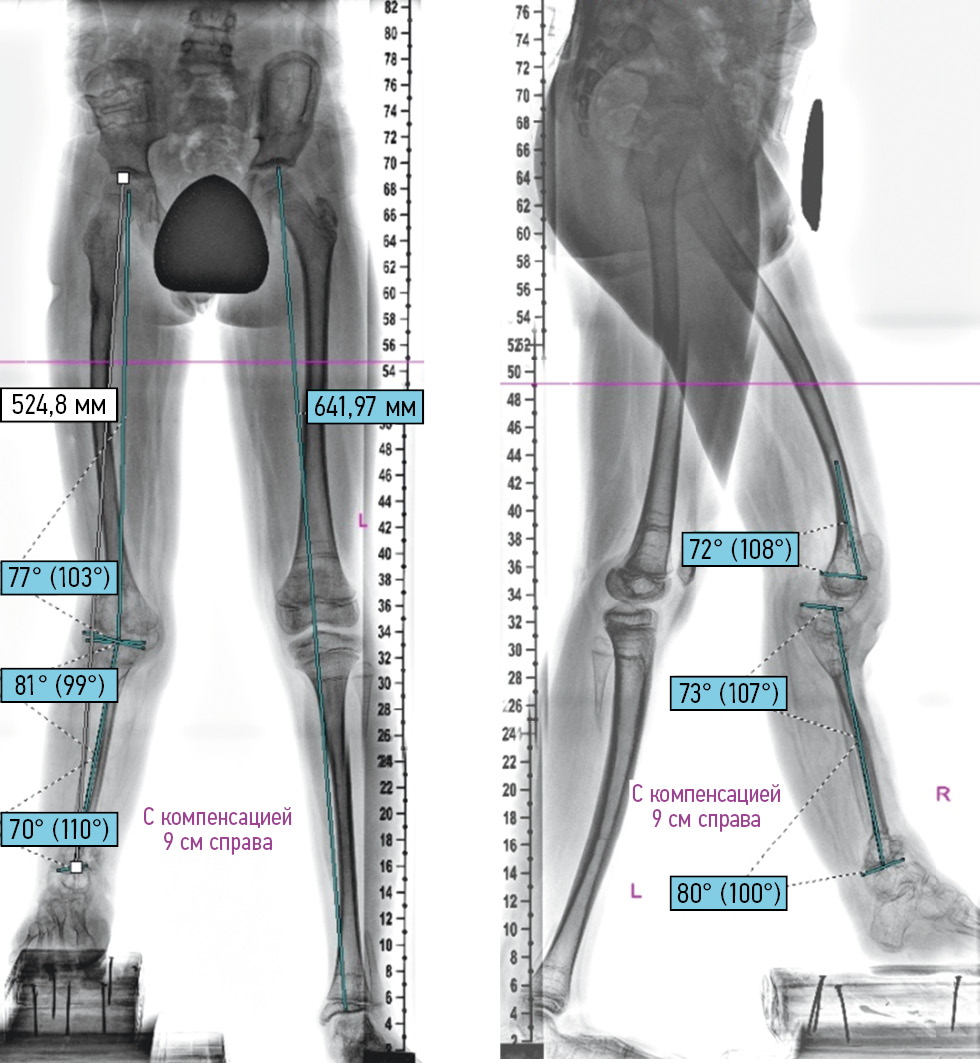

The analysis of panoramic radiographs of the lower extremities revealed the deformity components, namely, antecurvatum (LDFA 77°, DPFA 72°) in the distal metadiaphysis of the femur and valgus-recurvation (PMTA 99°, DMTA 70°, PPTA 107°, and DATA 84°) in the proximal and distal metadiaphyses of the tibia. These deformities were one of the components of the formation of flexion–extension contracture of the knee joint (flexion/extension 10°/0°/10°), which significantly impeded the function of the affected limb. Movements in the ankle joint were rocking. The affected lower limb shortened by 11.7 cm. Multiple scars of the skin and soft tissues were noted after previous surgical interventions (Fig. 7).

Fig. 7. Teleroentgenograms of the lower extremities in two views before the elimination of secondary deformities